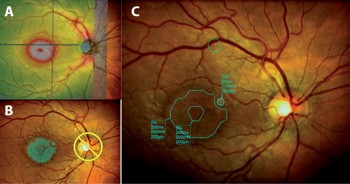

Fig 2. A. At baseline, OCT through the right fovea demonstrates subretinal fluid with small hyper-reflective pigment epithelial detachments. B. Following laser, there has been complete resolution of subretinal fluid at the fovea.

The results were notable from an anatomical standpoint. At two-month follow-up, OCT demonstrated complete resolution of subretinal fluid, while autofluorescence imaging confirmed preservation of RPE integrity at the fovea with no treatment-related damage.

However, functional outcomes were more complex. Despite excellent anatomical resolution, the patient reported minimal subjective visual improvement, with visual acuity remaining stable at 6/9. This likely reflects chronic photoreceptor changes from prolonged fluid accumulation, highlighting the importance of early intervention in CSCR.

Fig 3. A. At baseline, fundus autofluorescence images shows the extent of subretinal fluid as demarcated by hyperautofluorescence. B. Following laser, there is reduced hyperautofluorescence without any new areas of laser-induced changes, with the exception of a single titration laser spot at the superior arcade. Extent of residual changes reflect the chronicity of the oedema and helps explain the limited functional improvement

This case highlights several important principles. Chronic CSCR can be remarkably refractory to conventional treatments, including half-dose PDT. While half-dose PDT remains the gold-standard treatment for CSCR4, it carries risks of choroidal infarction and RPE atrophy that may result in worse outcomes than alternative approaches5. The combination of threshold treatment to undertreated areas with subthreshold treatment to the broader affected zone represents a nuanced approach that maximises therapeutic benefit while minimising collateral damage. The discordance between anatomical success and limited functional improvement underscores why early intervention remains crucial.